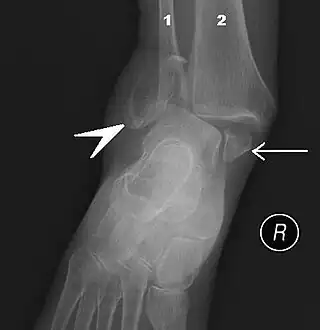

![]() Fractura en ambos lados del tobillo con dislocación vista en radiografía anteroposterior. (1) fíbula, (2) tibia, (flecha) maléolo medial, (cabeza de flecha) maléolo lateral | ||